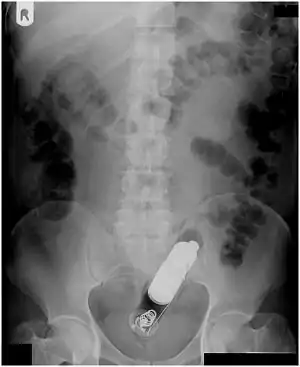

| Radiograph of a male abdomen with a vibrator inside the rectum | |